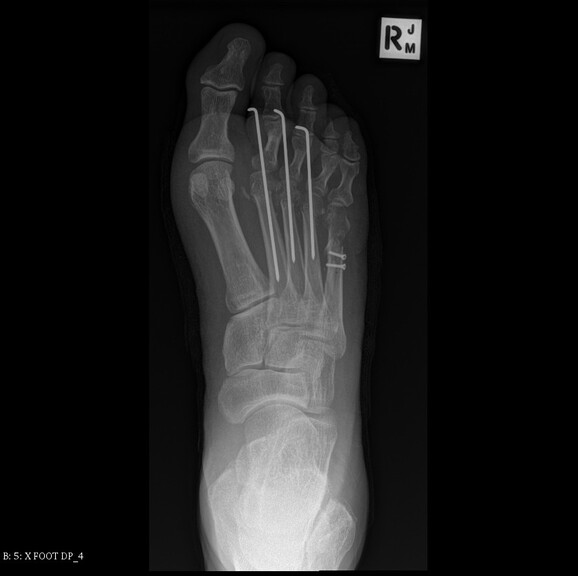

Right foot

Right foot 10/05/2017